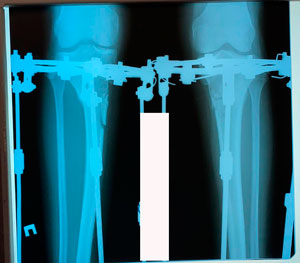

на фиксации

рентген в 60 дней.